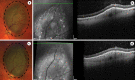

Introduction: There is an increase in pigmentation that occurs in many tumors following plaque brachytherapy for choroidal melanoma. Correctly distinguishing between increased pigment at the tumor border versus true growth is imperative. We performed a retrospective review of patients treated with I-125 brachytherapy for choroidal melanoma at our institution to study this phenomenon.

Methods: Records were reviewed for all patients undergoing plaque brachytherapy for uveal melanoma for a 5-year period (N = 195). Patients with iris and anterior tumors were excluded. Tumors treated more than 31 days after presentation were excluded. Fundus images for patients with increased pigmentation at any of the borders of the tumor at 6-month follow-up that extended beyond the initial pigmented margin were included (N = 20; 8 F, 12 M). Imaging at the last follow-up was reviewed, and it was confirmed that all tumors involuted appropriately with no evidence of local recurrence. The date of initial exam, time to treatment, and follow-up interval were recorded for each included patient.

Results: Twenty patients (10%) exhibited increased pigment deposition at any of the borders of the tumor at 6-month follow-up that extended beyond the initial pigmented margin. Average tumor thickness was 3.2 mm (1.3-5.1); average largest tumor basal diameter was 11.6 mm (7-15.5). Average time from diagnosis to treatment was 25 days (17-31). Average length of follow-up was 35 months (16-68). No patient developed recurrence during the duration of follow-up, and 1 patient had developed metastasis.

Conclusion: We describe the phenomenon of increased pigment deposition, "edge creep," at the borders of choroidal melanomas treated with plaque brachytherapy that gave the appearance of initial tumor growth but then subsequently remained stable over time. It is important that treating ocular oncologists be aware of this phenomenon to avoid unnecessary diagnosis of local recurrence.